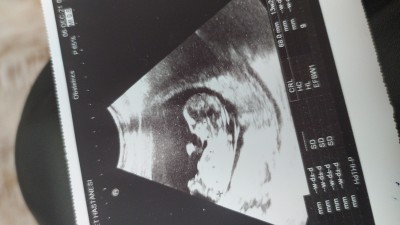

Çok merak ediyorum içinize ne doğuyor ben erkek hissediyorum ama  15+4

Hakkari'de oturuyoruz eşimin mesleğinden dolayı buradaki cihazlarda 20 haftaya kadar bişey göstermiyormus